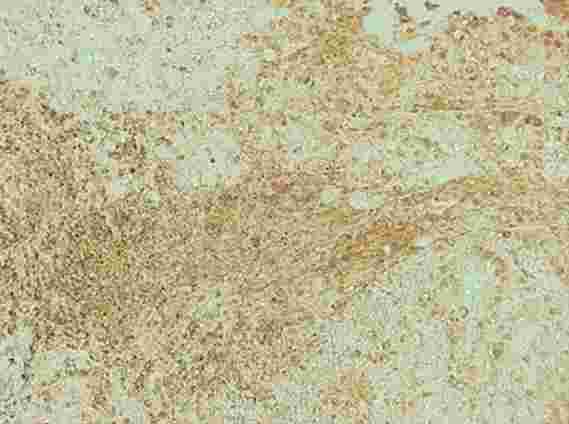

Wu等。证明尼古丁可通过刺激称为M2小胶质细胞的免疫细胞的形成来促进脑转移。在继续吸烟的肺癌患者的转移性脑肿瘤中可以观察到大量的M2小胶质细胞(棕色)。

患者大脑中的肿瘤含有大量的M2小胶质细胞,这是一种免疫细胞,其分泌几种能够增强肿瘤生长的分子。研究人员发现,尼古丁会刺激小鼠M2小胶质细胞的形成。从小鼠大脑中去除小胶质细胞可防止尼古丁诱发脑转移并提高肺癌小鼠的存活率。